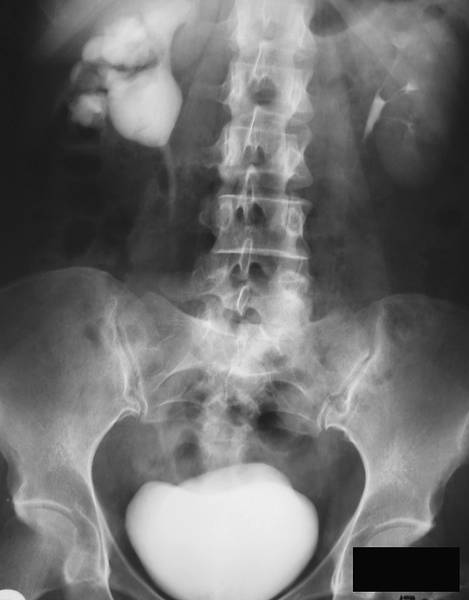

ЭКСКРЕТОРНАЯ УРОГРАФИЯ

Экскреторная урография (Binz, Roseno, 1929) основана на способности почек выделять контрастное вещество, введённое внутривенно (рис.).

Нормальная экскреторная урограмма.

Помимо определения функционального состояния почек, она позволяет получить представление о морфологическом строении мочевыводящих путей, но для этого функция почек должна быть удовлетворительной. По мере её снижения плотность тени контрастного вещества на рентгенограмме также уменьшается. Для проведения экскреторной урографии раствор контрастного вещества вводят в одну из периферических вен. В настоящее время применяют такие жидкие контрастные препараты, как амидотризоевая кислота℘, йогексол, йопромид и йодиксанол. При хорошей функциональной способности почек первую урограмму выполняют спустя 5–7 мин после введения контрастного вещества, у пациентов со сниженной функцией почек — спустя 10–12 мин. Следует обращать внимание на качество урограмм, степень заполнения контрастным веществом разных отделов ВМП, как с правой, так и с левой стороны. В зависимости от результатов первой урограммы последующие снимки выполняют на 15-й и 30-й мин. Если с одной стороны ВМП отчётливо выполнены контрастным веществом, а с другой тень контрастного вещества отсутствует или видна тень расширенных чашечек, то необходимы поздние снимки (через 1–2 ч).

При интерпретации урограмм следует обращать внимание на интенсивность теней паренхимы почек, их величину, форму и положение, начало выделения контрастного вещества в ЧЛС. Кроме того, нужно оценить плотность теней контрастного вещества в лоханках, чашечках и мочеточниках, наличие изменений в ВМП, время поступления контрастного вещества в мочевой пузырь и характер его заполнения. При экскреторной урографии тень рентгенопозитивного камня усиливается. Рентгенонегативный камень даёт дефект наполнения. При нарушении оттока мочи из почки всегда возникает расширение ВМП выше места окклюзии. Наиболее яркая иллюстрация этого — симптом Лихтенберга (рис.), который отмечают при камне мочеточника. Дилатация ЧЛС и мочеточника над камнем напоминает указующий перст, что дало второе название этому симптому — «симптом указательного пальца». Нужно помнить, что абсолютным доказательством камня мочеточника считают обнаружение симптома Лихтенберга на снимках в двух проекциях.